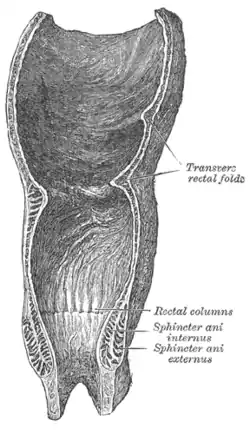

The interior of the anal cami and lower part of the rectum, showing the columns of Morgagni and the anal valves between their lower ends. (Pectinate line visible but not labeled.) | |

The pectinate line (dentate line) is a line which divides the upper two-thirds and lower third of the anal canal. Developmentally, this line represents the hindgut-proctodeum junction.

It is an important anatomical landmark in humans, and several distinctions can be made based upon the location of a structure relative to this line: